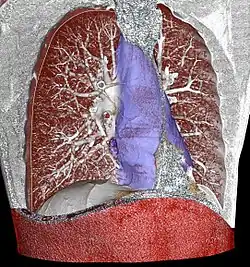

| |

| Mediastinum | |